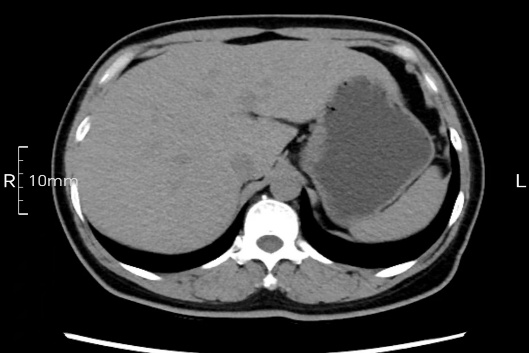

看看下面三幅便知遵醫(yī)囑的重要性。

沒(méi)禁食,胃內(nèi)全是食物,導(dǎo)致胃壁顯示不清。